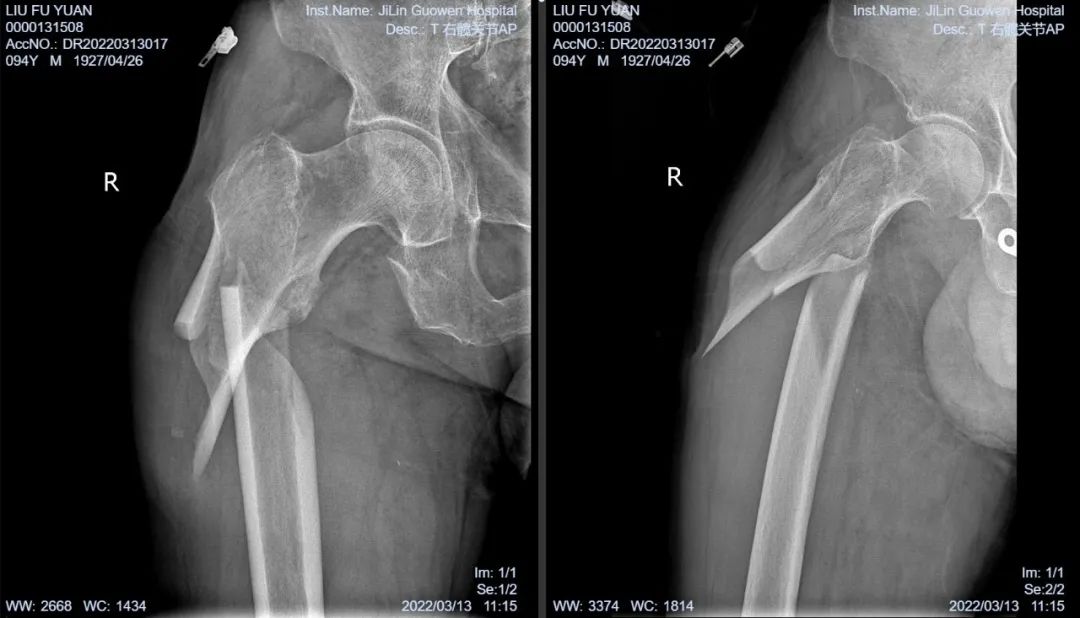

3月13日伴著急促的腳步聲、轆轆的車(chē)輪聲,夾雜著患者痛苦的呻吟聲,一位94歲的高齡老人被急診科醫(yī)護(hù)人員緊急送至骨科療區(qū)。這是怎么回事?呂國(guó)褔主任帶著值班醫(yī)生在做好防護(hù)措施后,第一時(shí)間來(lái)到患者病床前,經(jīng)急診科醫(yī)生診斷告知為 “股骨近端粉碎性骨折”,患者右大腿近端嚴(yán)重畸形,骨折端已經(jīng)刺穿前方肌肉直達(dá)皮下,局部皮膚高高隆起,局部皮膚有挫傷灶,呈青紫色,皮膚變薄,皮膚外可明顯觸及骨折斷端,右股骨X線(xiàn)片示:右股骨近端粉碎性骨折,斷端移位明顯,斷端銳利,近斷端位于前方皮膚下,局部皮膚隆起?;颊咛弁磩×?,痛苦難耐,測(cè)生命體征:血壓:220/110mmHg。